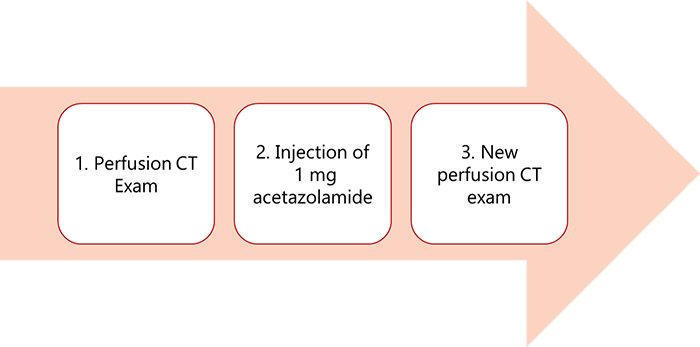

A common approach: Acetazolamide tolerance test is the hemodynamic stress test where you start with a perfusion CT exam then an injection of 1mg of acetazolamide, followed by a new perfusion CT series. The perfusion CT will give a good image quality to detect any abnormal region and the ability to know the values for CBV and MTT.